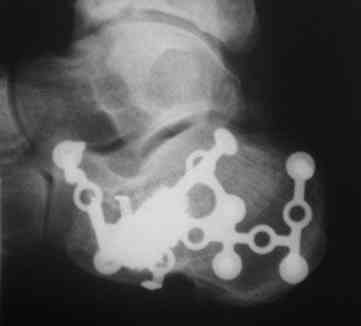

И чем вам не нравится ORIF?... Не нашел первоначальный снимок, но очень похож на представленный. Есть только после операции. Через 6 нед. встал и пошел без боли!

IMG_0221.JPG

Точность репозиции суставной поверхности задней фасетки суставной поверхности пяточной кости на представленной вами рентгенограмме вызывает глубокие сомнения, так же как и конечный результат лечения в долгосрочной перспективе. По всей вероятности, у больного был перелом пяточной кости по классификации Sanders типа II A. Часть суставной поверхности задней фасетки, оставшаяся с sustentaculum пяточной кости (короткая линия на вложении, соответствующая субхондральному слоя репонированного фрагмента) находится на месте. А вот большая часть суставной поверхности так и осталась компримирована (длинная линия на вложении, соответствующая субхондральному слою компримированного фрагмента). При репозиции эти две линии должны совпадать. После репозиции, компримированный фрагмент следовало фиксировать к sustentaculum отдельным винтом (не всегда просто точно попасть). Пяточная пластина смещена к пяточному бугру, что не позволило фиксировать к ней самый проблемный участок пяточной кости – суставную поверхность. Не лишней здесь после репозиции была бы и костная пластика.

С уважением, VlaD.

calcaneus 3.jpg